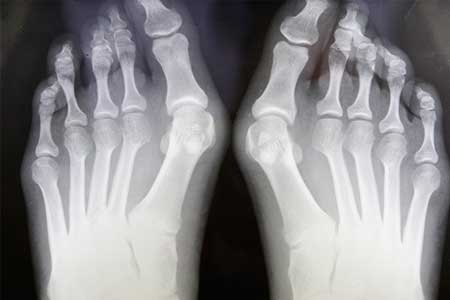

The physicians of Bloomfield Foot Specialists care for people of all ages. Common podiatric disorders are bunions, heel pain, hammertoes, neuromas, ingrown nails, warts, corns and calluses. Our physicians render care for sprains, fractures, infections, diabetic foot infections and injuries of the foot and ankle. We offer in-office and hospital treatment for surgical care.